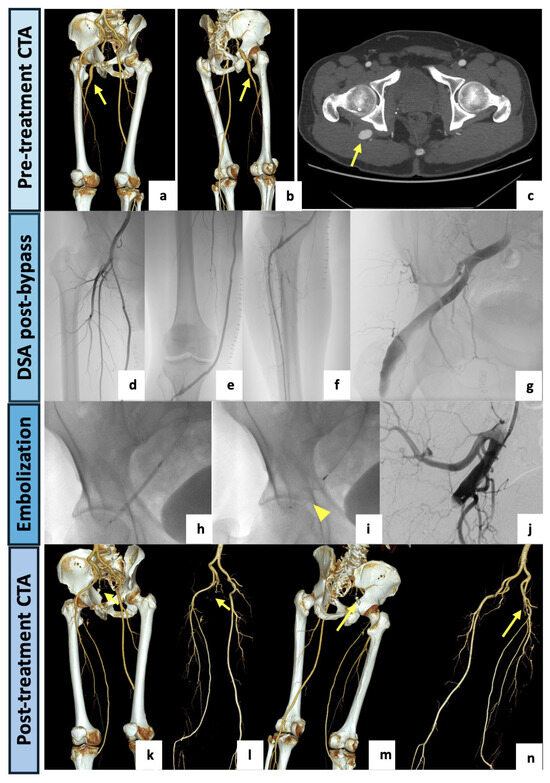

2.1. Case 1

A 79-year-old woman was admitted to our hospital for intense right flank and buttock pain with a burning sensation in the gluteal region radiating down the back of her right lower limb and preventing her from walking normally. She had no significant medical history other than experiencing several similar episodes of pain. Physical examination revealed stable vital signs, palpable and symmetric femoral pulses, normal distal bilateral perfusion, no claudication or ulcers and no clinical signs of superficial or deep vein thrombosis. Neurological examination revealed no motor or sensory deficit. Blood tests on admission were unremarkable. At DUS examination of the lower limbs, a normal right common femoral–external iliac axis was detected, with a regular right ankle–brachial index. The left-limb DUS showed a regular common femoral–external iliac axis with a hypoplasic SFA and popliteal low flow pattern. The ankle–brachial index was bilaterally normal. A CTA examination (Figure 2) showed a right PSA originating from the internal iliac artery, running through the greater sciatic foramen, entering in the thigh and continuing as a popliteal artery, supplying the distal arteries of the leg. The PSA was associated with a normal SFA (type 1). An aneurysmal degeneration of the PSA, measuring 57 mm in the maximal caliber with poor mural thrombus, was found in the posterior aspect of the thigh. On the left limb, a fully developed and completely occluded PSA with a hypoplastic SFA (type 2A) was detected. The popliteal artery was supplied by collateral pathways originating from the hypoplastic SFA and the deep femoral axis. Having confirmed that the patient was not suffering from left lower limb claudication interfering with normal activities, the case was collegially discussed and evaluated as eligible for endovascular management of the right aneurysmatic PSA. The procedure was performed in our institutional angiosuite (flat-panel C-arm system, Artis zee, Siemens Healthcare, Erlangen, Germany). A right common femoral artery access was performed under local anesthesia (10 mL of Mepivacaine 2% solution) and a 6F-sheat (45 cm) introducer sheath was positioned. A left humeral access with a long 4F-sheat (60 cm) was also utilized for diagnostic angiographies. The left femoral access was avoided due to a focal chronic dissection in the left external iliac artery, as shown by the CTA. The right PSA was selectively catheterized, and the aneurysm was embolized with the “sandwich technique” to avoid retrograde recanalization. Two vascular plugs (AVP—Abbott Medical, North Plymouth, MN, USA) were deployed in the outflow (12 mm) and in the inflow vessel (14 mm). The final angiograms showed a nearly complete occlusion of the aneurysm (small residual slow flow). The procedure was successfully completed without complications. The patient was discharged after two days with single antiplatelet therapy. At the clinical follow-up, a complete disappearance of symptoms and no further need for pain medication were confirmed, and the 1-month CTA follow-up examination showed the complete exclusion of the PSA aneurysm.

Figure 2.

(a) VR reconstruction of the preoperative CTA showing a right PSA originating from the internal iliac artery (arrow), continuing as a popliteal artery and associated with a normal SFA (type 1). (b–f) Three-dimensional reconstructions, with and without bone structures, and axial maximal intensity projections showing a huge aneurysmal degeneration (57 mm in the AP caliber) of the PSA in the posterior aspect of the thigh (arrows). (g) Intraprocedural selective angiography of the right PSA performed after obtaining a left humeral access with a 4F-sheat (60 cm), confirming a large aneurysm. (h,i) Intraprocedural images obtained after right common femoral artery access with a 6F-sheat and right PSA selective catheterization. (j,k) Aneurysm exclusion with “sandwich technique”: embolization through two vascular plugs deployed in the outflow and in the inflow vessel (arrowheads). (l) At final angiography, a nearly complete occlusion of the aneurysm (small residual slow flow) was documented. (m–p) VR reconstruction of postoperative CTA (1-month), demonstrating the complete exclusion of the PSA aneurysm. Both inflow and outflow were occluded by vascular plugs (arrows).